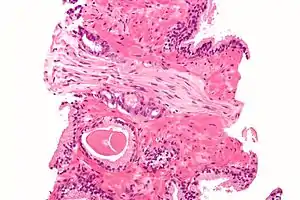

Histopathologic diagnosis

A histopathologic diagnosis mainly includes assessment of whether a cancer exists, as well as any subdiagnosis, if possible. Histopathologic subdiagnosis has implications for the possibility and methodology of Gleason scoring.[85] The most common histopathological subdiagnosis is acinar adenocarcinoma, constituting 93% of diagnoses.[86] The most common form of acinar adenocarcinoma, in turn, is "adenocarcinoma, not otherwise specified", also termed conventional, or usual acinar adenocarcinoma.[87]

Gleason score

The Gleason grading system is used to help evaluate the prognosis and helps guide therapy. A Gleason score is based upon the tumor's appearance.[89] Cancers with a higher Gleason score are more aggressive and have a worse prognosis. Pathological scores range from 2 through 10, with a higher number indicating greater risks and higher mortality.

After a biopsy, a pathologist examines the samples under a microscope. If cancer is present, the pathologist reports the grade of the tumor. The grade tells how much the tumor tissue differs from normal prostate tissue and suggests how fast the tumor is likely to grow. The pathologist assigns a Gleason number from 1 to 5 for the most common pattern observed under the microscope, then does the same for the second-most common pattern. The sum of these two numbers is the Gleason score. The Whitmore-Jewett stage is another method.